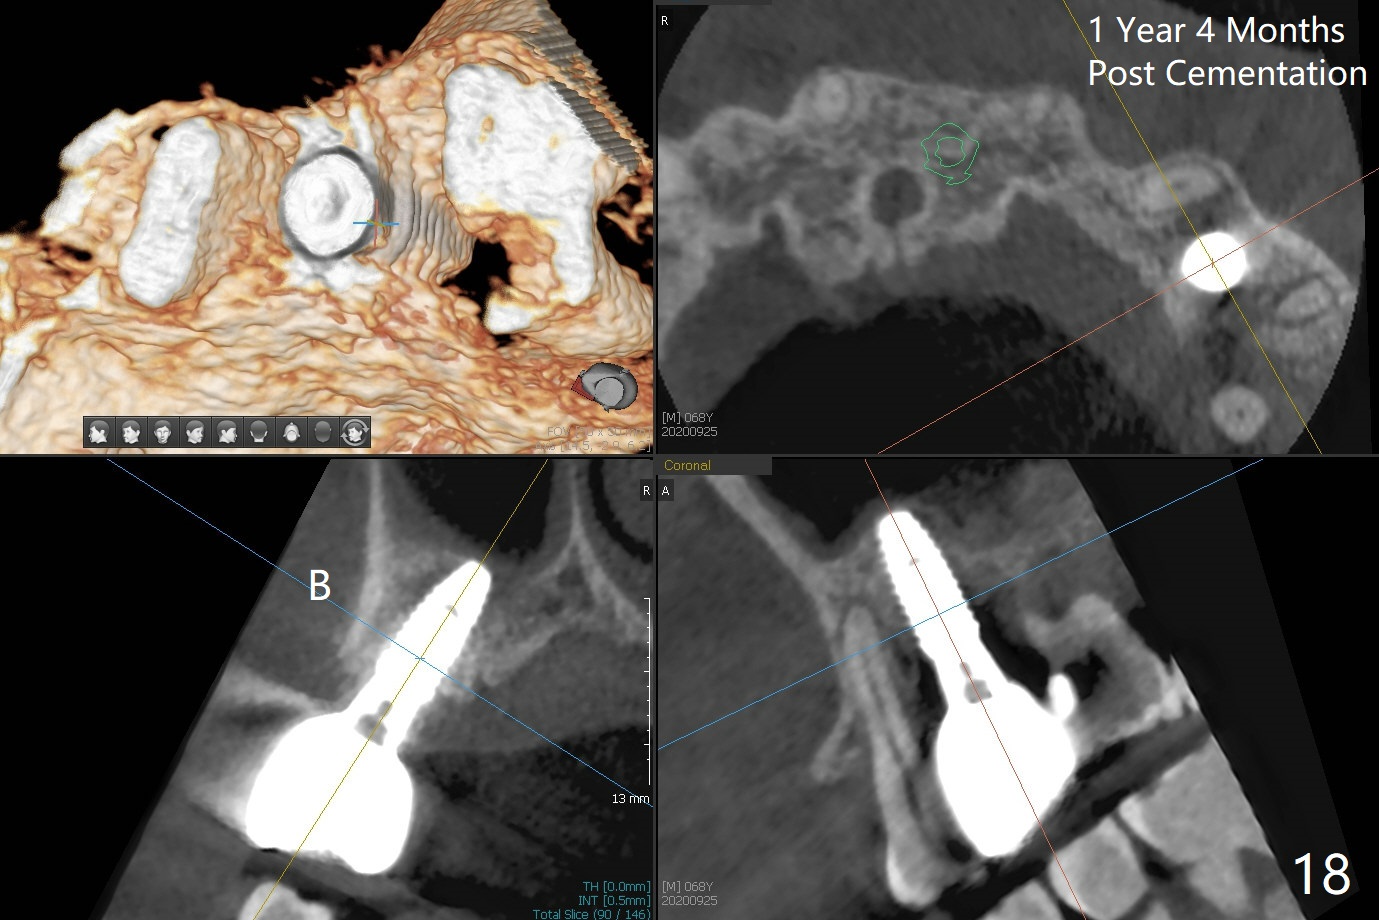

When the initial osteotomy is off substantially (Fig.4), an osteotomy should be established de novo and as early as possible (Fig.14) so that subsequent osteotomy will not relapse to a great extent. More ideally, the initial osteotomy should be planned correctly (Fig.15,16) with sacrifice of the bone height. Nearly 1 month postop, the 4.5x5.5(5) cementation abutment is loose. When it is removed, the patient feels pain from the implant. A 5.5x6 mm healing abutment is placed instead. The implant osteointegrates with trabecular pattern in the sinus 9 months postop (Fig.20 *). The gingiva around the crown at #13 is healthy 1 year 4 months post cementation (Fig.18). Check the distal surface of #13 for bone loss if the tooth #14 is to be extracted.